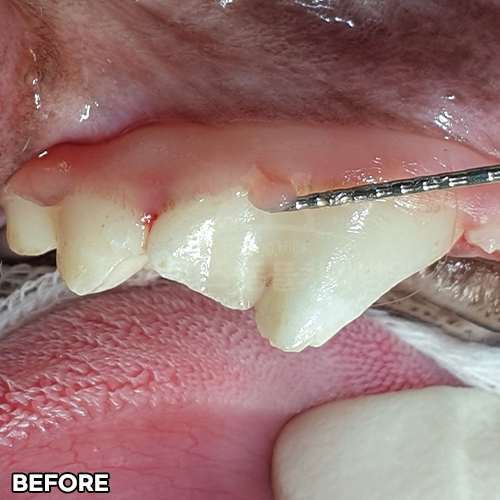

[강아지 치아의 구멍 레진치료 후 2주 경과]